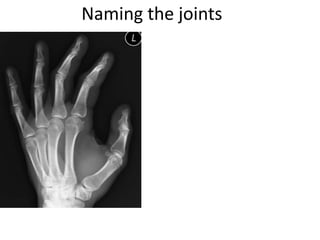

This document provides an overview of hand anatomy including:

- Naming the bones, joints, tendons, nerves and skin landmarks of the hand and wrist.